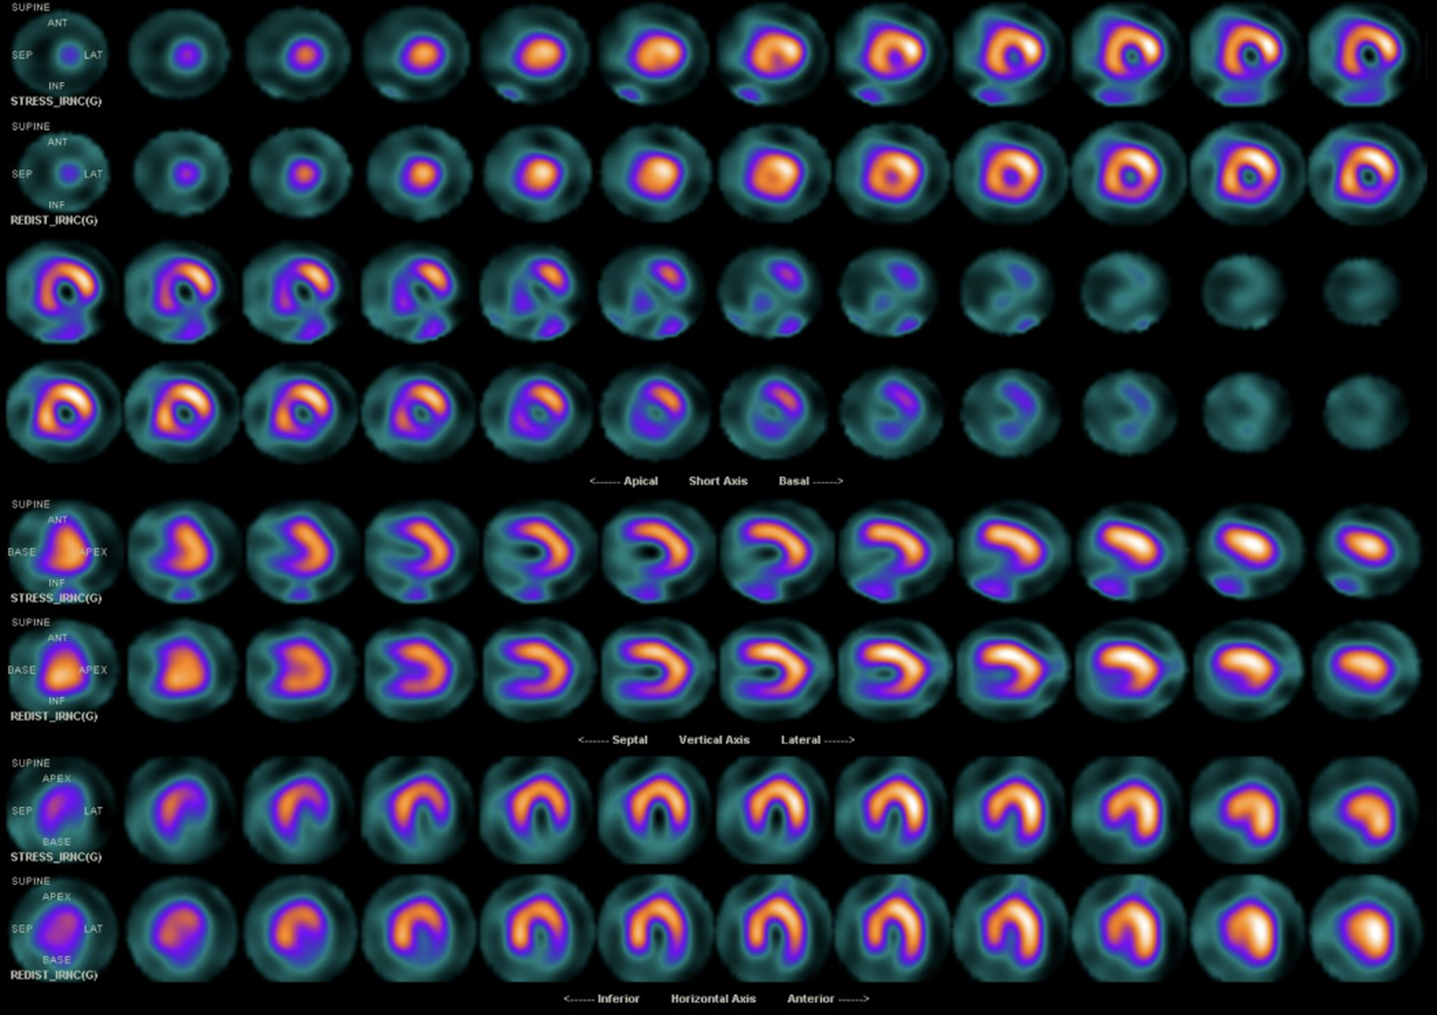

The laboratory test showed white blood cell count (WBC) of 7.8x10^3/uL, hemoglobin (Hb) level of 15.1gm/dl, platelet count of 181x10^3/uL.The glucose level is 98mg/dL, The liver enzyme levels show GOT (AST) at 19 U/L and GPT (ALT) at 22 U/L. Lipid panel results include HDL-C at 44mg/dL, LDL-C at 62mg/dL, triglycerides at 101mg/dL.Creatinine level of 0.75 mg/dL (eGFR:108.53) Tl-201 myocardial perfusion scan showed abnormal uptake in inferior, inferolateral, and septal wall